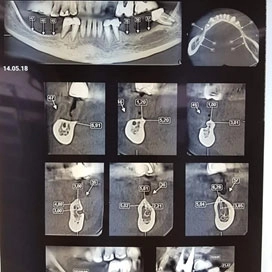

Латерализация и постеориоризация нижнечелюстного нерва

Пациентка C. 48 лет.

С помощью Пьезотома проведена операция латерализации и постеориоризации нижнечелюстного нерва в области 35-37 и 45-47.

С помощью боров и костных конденсоров XiVE сформированы 7 лож имплантатов. Введены имплантаты XiVE в области 35, 36, 37 – D3,4/L13; 45, 46, 47 – D3,4/L9,5; 44 – D3,8/L9,5; 43 – D3,8/L11.